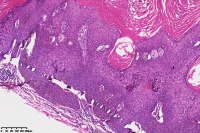

脂溢性角化症伴皮角?

性别

女

年龄

49岁

手臂皮肤组织

图4

脂溢性角化病